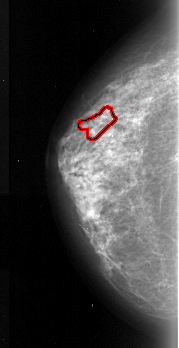

FILE: A_1032_1.LEFT_MLO.OVERLAY

TOTAL_ABNORMALITIES 1

ABNORMALITY 1

LESION_TYPE CALCIFICATION TYPE FINE_LINEAR_BRANCHING DISTRIBUTION LINEAR

ASSESSMENT 4

SUBTLETY 3

PATHOLOGY MALIGNANT

TOTAL_OUTLINES 1

BOUNDARY